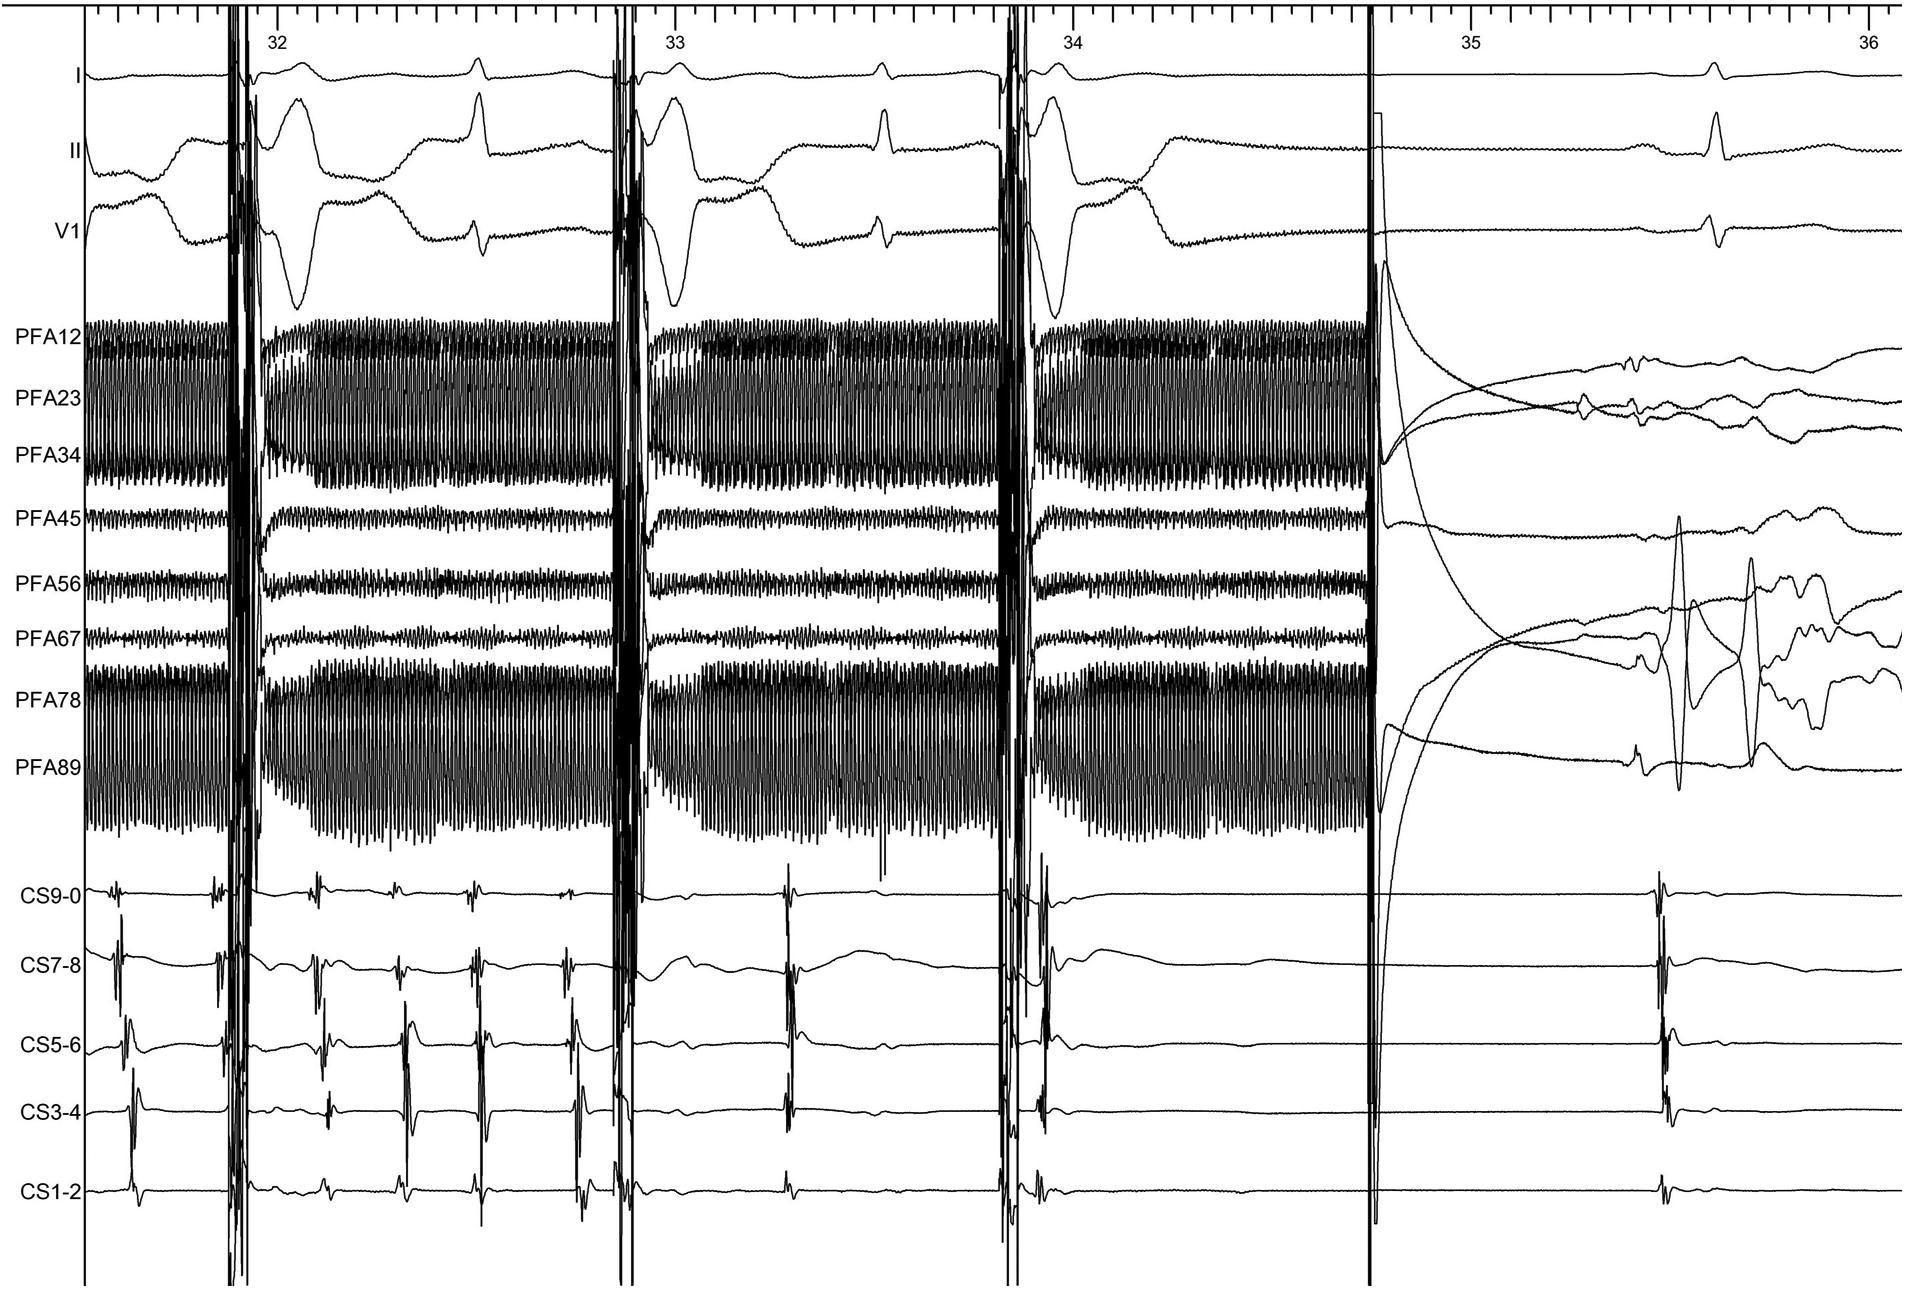

The patient presented sinus rhythm at the beginning of the procedure. However, atrial fibrillation recurred during left atrial mapping using a PentaRay catheter (Biosense Webster, Inc., Irvine, CA, USA). After all pulmonary veins were successfully isolated using an 8-F circular pulsed field ablation catheter (Shineyo Medical, Shanghai, China), atrial fibrillation persisted. The circular pulsed field ablation catheter was then placed within the superior vena cava, revealing some brief fractionated potentials and a local atrial fibrillation cycle length shorter than that in the coronary sinus (Figure 1). The atrial fibrillation terminated after a pulsed field ablation catheter discharge at the superior vena cava (biphasic, 1,400 V) (Figure 2). The left atrial voltage map pre- and post-pulsed field ablation is shown in Figure 3. The total procedure time was 2 h with a superior vena cava ablation time of 20 s.

Figure 2. The atrial fibrillation terminated after the pulsed field ablation catheter discharged at the superior vena cava. The electrocardiogram was recorded at a speed of 100 mm/s.